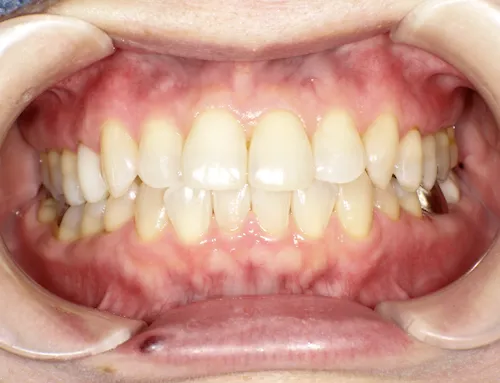

歯科の医療ホワイトニング

痛くない・しみないのに、45分で白くなる。